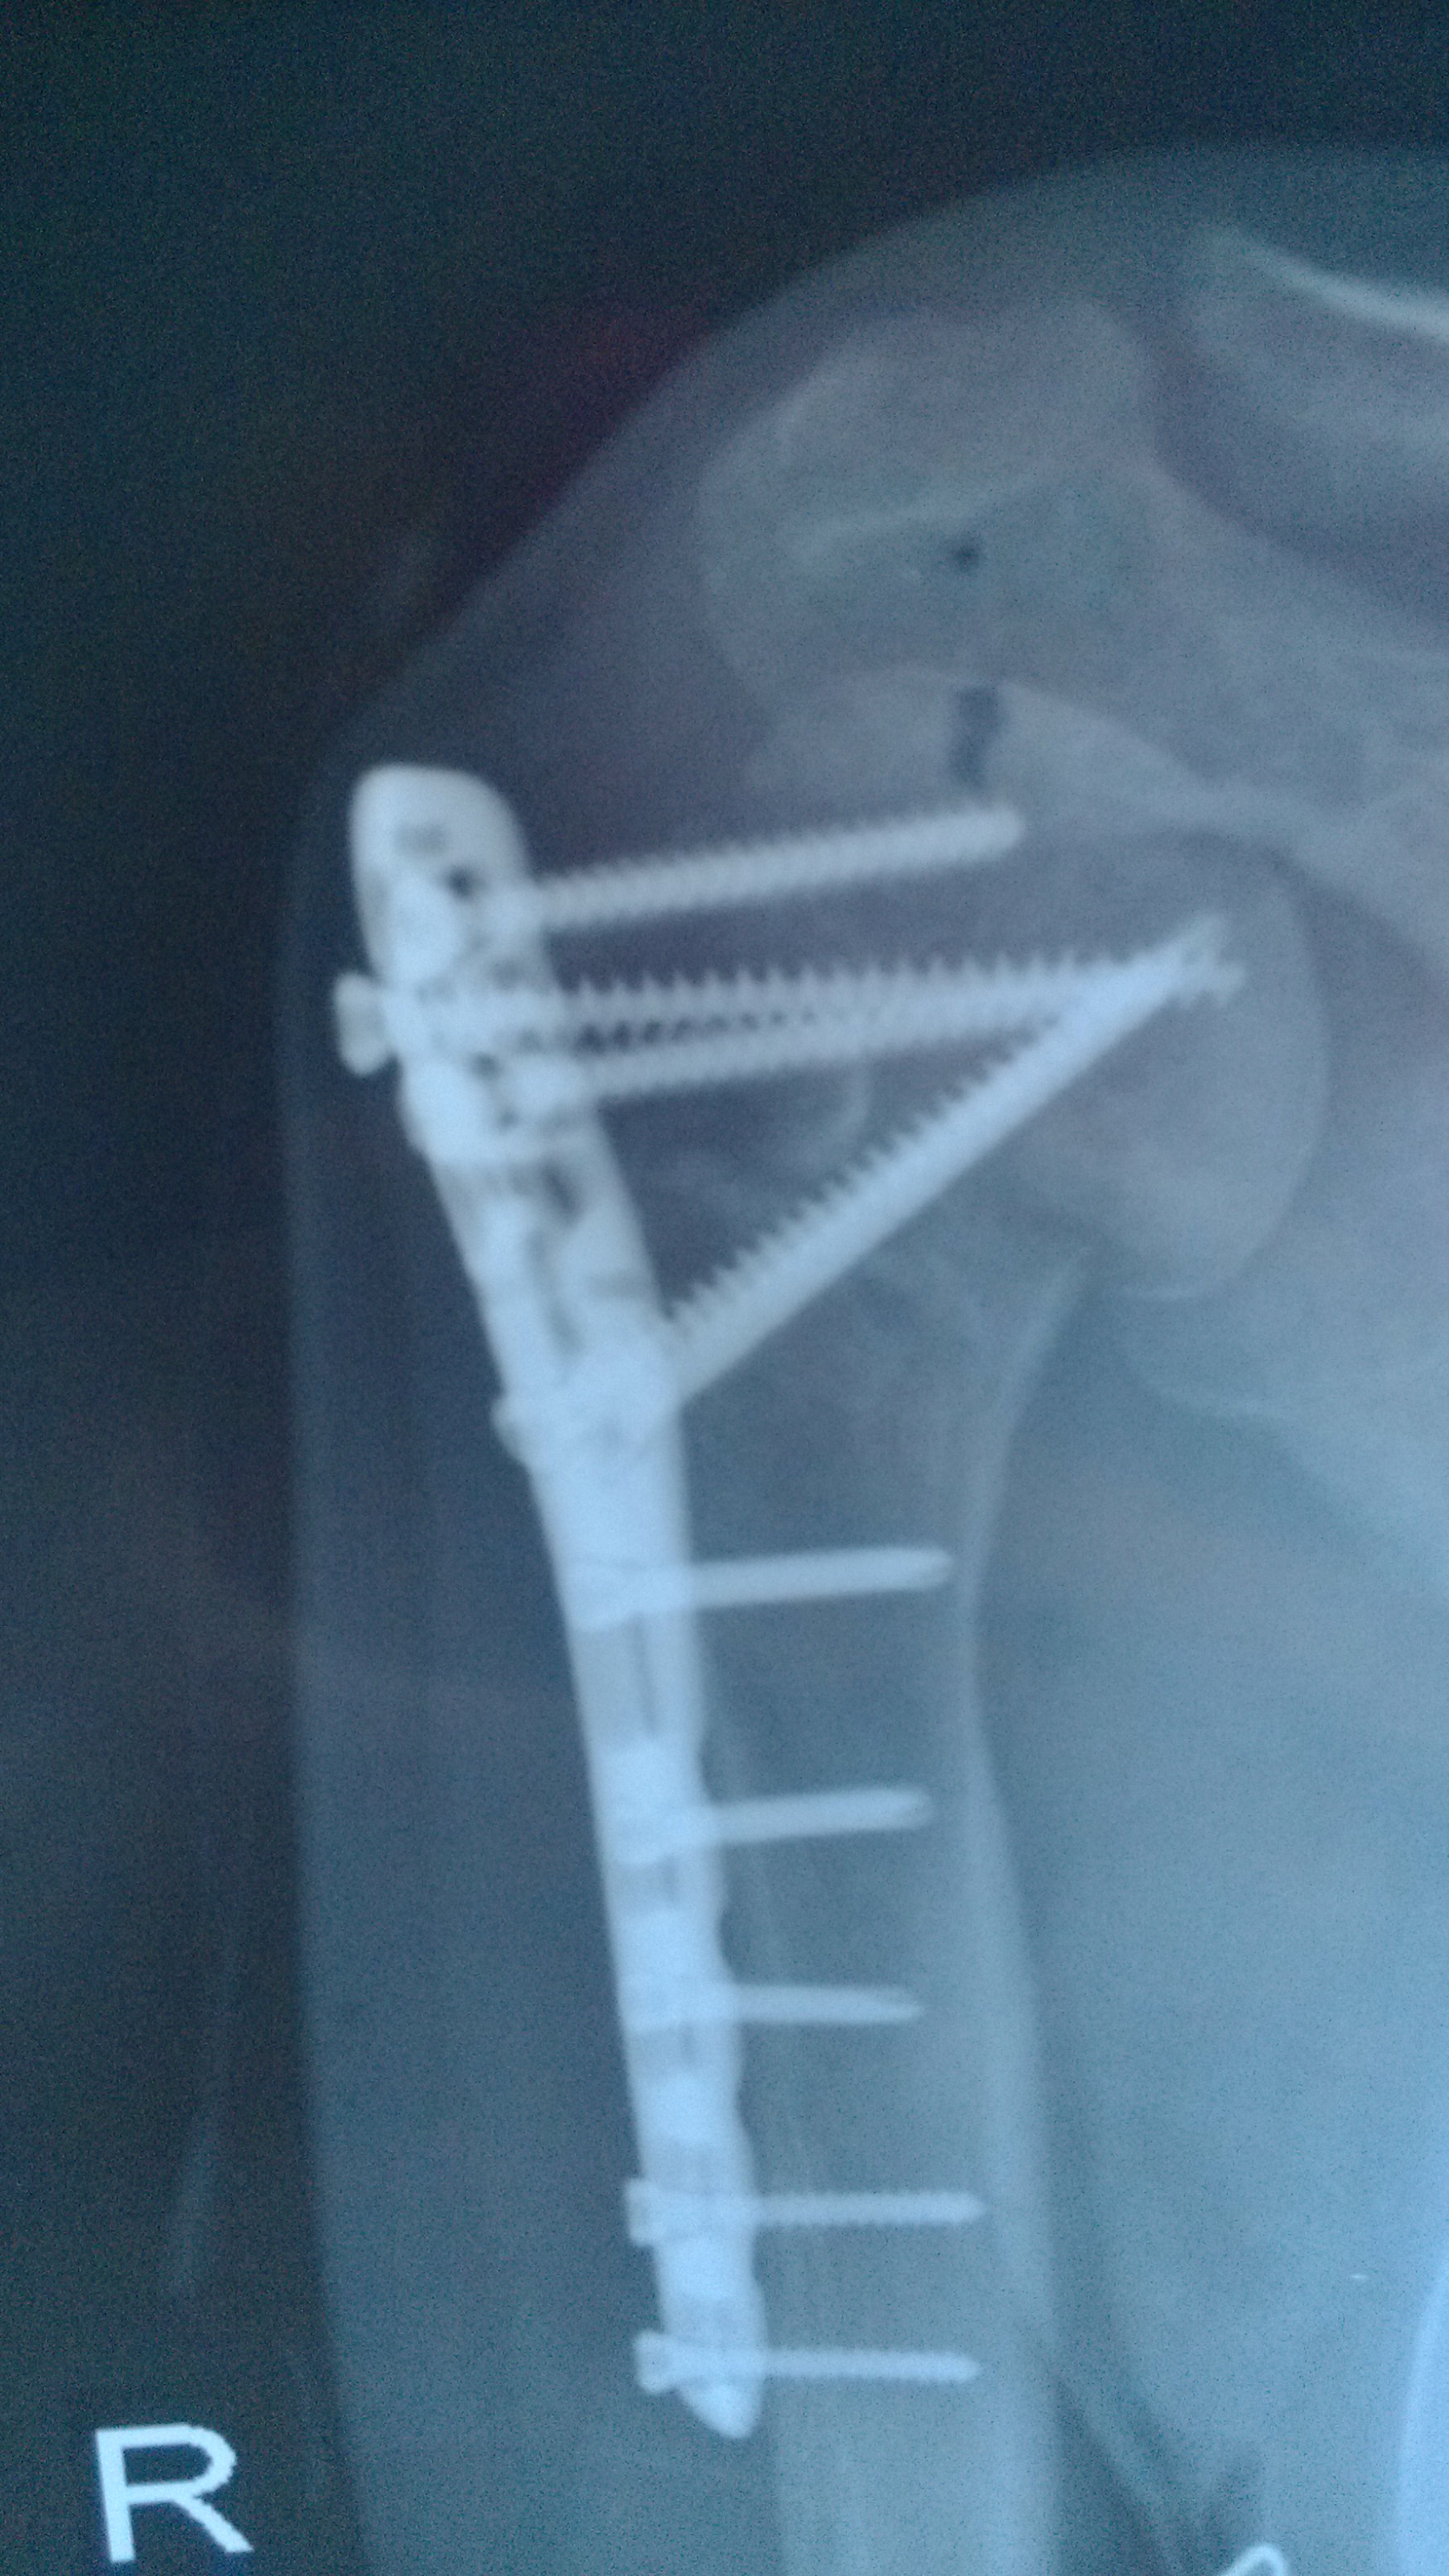

H hailiang真人 声名鹊起 正式会员 注册 2012/11/07 帖子 352 获得点赞 11 声望 0 2013/03/17 #26 这个片子提示,1骨折线高,提示血循损伤较重,2对接不理想 ,可能头与干对接中产生了旋转,不过实际操作很难都对上,很多骨折百分之五十对位即能长上。3螺钉偏多。螺钉为了固定,但螺钉本身对血循是一个破坏,按手术者言,三点固定,也是按章操作没错。所以,传统中医伤科主张尽量闭合复位,减少损伤血循,可是操作在人。这个病人运气不好,应该是外伤时已有骨折,是没拍片就复位还是拍片没看出来【有时新鲜骨折线不易看出】复位,还是外伤后,头干已分离不得而知。总之预后堪忧。

这个片子提示,1骨折线高,提示血循损伤较重,2对接不理想 ,可能头与干对接中产生了旋转,不过实际操作很难都对上,很多骨折百分之五十对位即能长上。3螺钉偏多。螺钉为了固定,但螺钉本身对血循是一个破坏,按手术者言,三点固定,也是按章操作没错。所以,传统中医伤科主张尽量闭合复位,减少损伤血循,可是操作在人。这个病人运气不好,应该是外伤时已有骨折,是没拍片就复位还是拍片没看出来【有时新鲜骨折线不易看出】复位,还是外伤后,头干已分离不得而知。总之预后堪忧。

奥 奥德赛 声名鹊起 正式会员 注册 2012/11/14 帖子 197 获得点赞 1 声望 0 年龄 57 2013/04/25 #28 王家祥 说: 将你的内服方子改动一下。 黄芪120克,当归24克,土鳖虫150克,海马15克,脆蛇50克,川续断100克,骨脆补 点击展开... 王老师:你好! 前月找你帮忙看了这例肩关节肱骨头脱落病例,按照你所开药方服用了一个月的丸子药,其中螃蟹是单独打粉服用,量比处方剂量大,此外,还按你的介绍用了艾灸骨头断裂处,同时服用了汤药,还用了中药煎汤处敷。几种方法同用,至今已有一月余,今天上午又去医院照了片,诊断结论如下:右侧肱骨外科颈骨折内固定术后,骨折线模糊,内固定物未见移位及脱位 照片的老师说长了点,骨头没有变形和脱位。 请王老师百忙之中帮忙再诊断一下,同时就继续服药帮忙处一下方,谢谢了!!! 附件 IMG_20130425_123412.jpg 1 MB 查看: 24 IMG_20130425_123452.jpg 1 MB 查看: 29

王家祥 说: 将你的内服方子改动一下。 黄芪120克,当归24克,土鳖虫150克,海马15克,脆蛇50克,川续断100克,骨脆补 点击展开... 王老师:你好! 前月找你帮忙看了这例肩关节肱骨头脱落病例,按照你所开药方服用了一个月的丸子药,其中螃蟹是单独打粉服用,量比处方剂量大,此外,还按你的介绍用了艾灸骨头断裂处,同时服用了汤药,还用了中药煎汤处敷。几种方法同用,至今已有一月余,今天上午又去医院照了片,诊断结论如下:右侧肱骨外科颈骨折内固定术后,骨折线模糊,内固定物未见移位及脱位 照片的老师说长了点,骨头没有变形和脱位。 请王老师百忙之中帮忙再诊断一下,同时就继续服药帮忙处一下方,谢谢了!!!